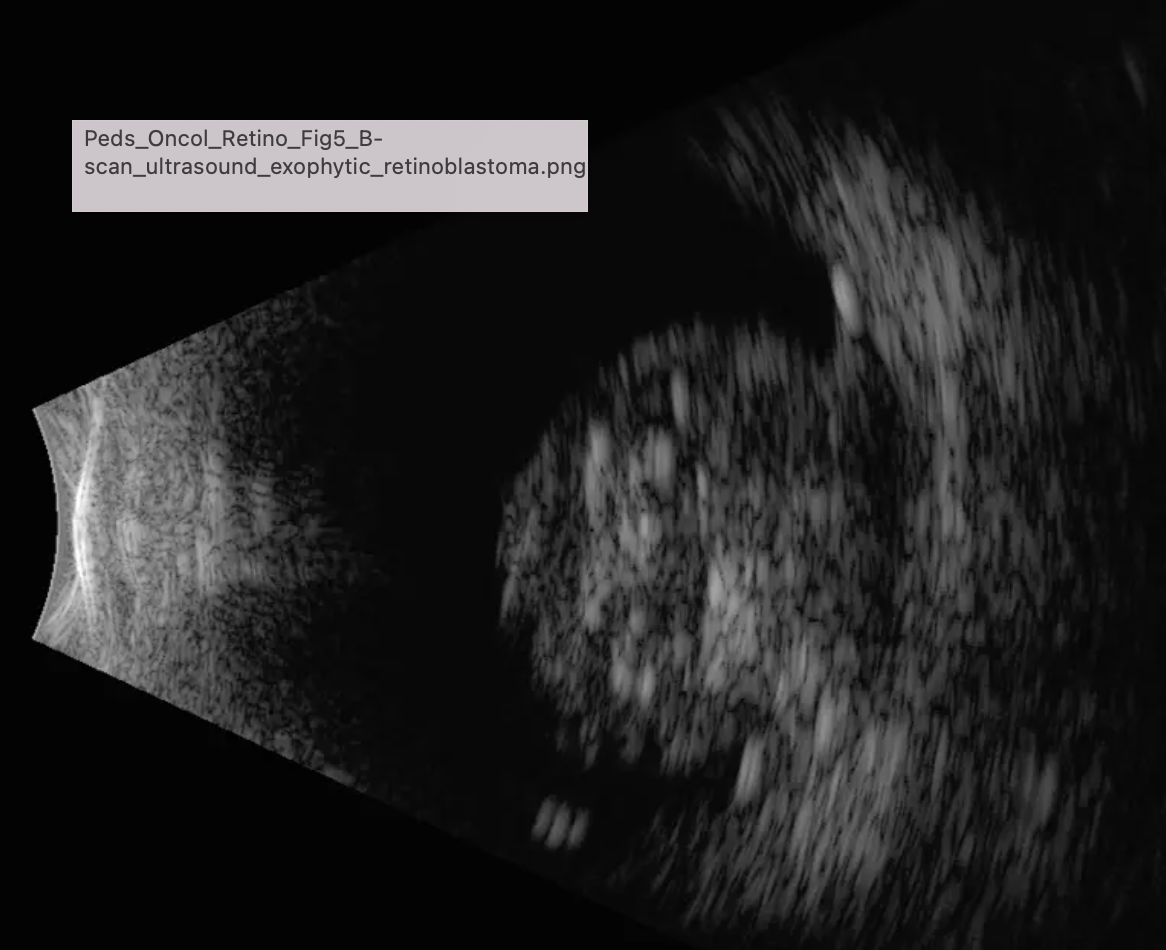

Confirm diagnosis w/exam under anesthesia:

B-scan

MRI